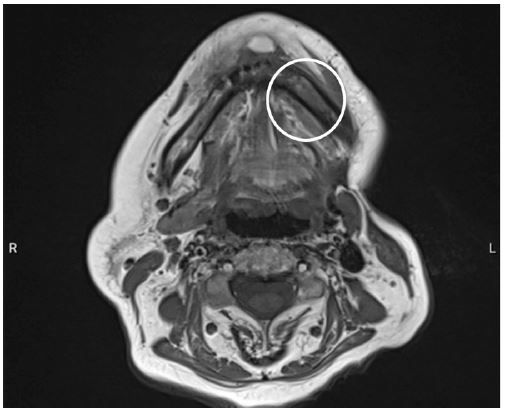

Figure 3: Transversal section on MRI, revealing a left sided increased signal intensity at the left mandibular corpus on T2-weighted images, consistent with mandibular osteomyelitis.

The left submandibular salivary gland was removed due to the formation of an abscess. Histopathological examination confirmed supportive inflammation with an early granulomatous transformation. Subsequently, an episode of recurrent cervical collection necessitated a week-long admission to the Ear, Nose, Throat (ENT) department, where an Orthopantomograph (OPT) revealed tooth element 37, with no evidence of infection noted. Approximately four weeks post-admission, infliximab administration was interrupted again, due to another recurrence of the cervical abscess that mandated further drainage. Cultures revealed predominant white blood cells with minimal red blood cells. Streptococcus constellatus, sensitive to ampicillin, was once more identified, and the wound continued to produce pus. Two months later, the patient reported pain localized to the left mandibular region. A subsequent CT-scan showed soft tissue air inclusions, without noteworthy osteomyelitic changes or periosteal reactions. Notably, tooth element 37 was absent on this scan, having been previously extracted by the general dentist. Within nine days, the patient sought emergency care due to unbearable pain upon eating and drinking from a recurrent abscess, alongside long-standing numbness along the left mandible, anamnestically revealing incorrect occasional self-administration of amoxicillin/clavulanic acid as a means of pain relief. A Magnetic Resonance Imaging (MRI) scan confirmed left-sided osteomyelitis of the mandible, encouraging the patient’s referral to our department at the university hospital (Figures 3 and 4).